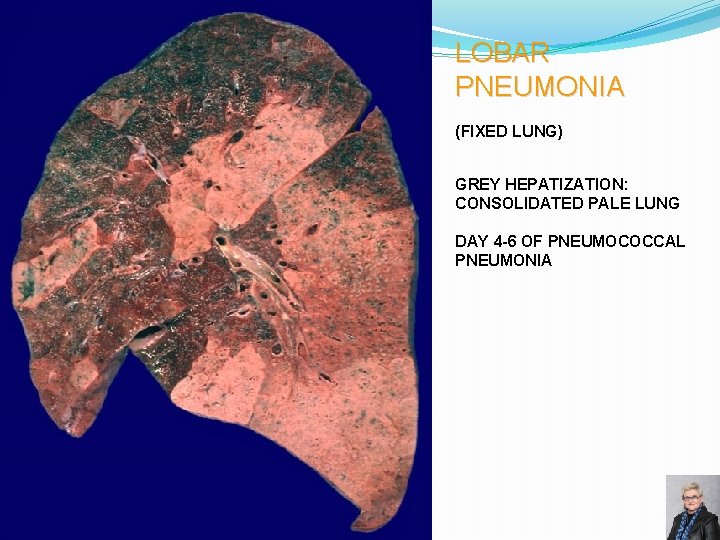

LOBAR PNEUMONIA; CLASSIC STAGES (AS SEEN IN PNEUMOCOCCAL PNEUMONIA) Congestion: �Heavy, boggy, red, hyperemic lungs with many bacteria but few neutrophils Red hepatization: �Massive confluent alveolar filling with RBCs, neutrophils, and fibrin Gray hepatization: �Disintegrating RBCs and fibrinopurulent exudate fill alveoli Resolution: �Macrophages mop up debris and normal function returns 59

LOBAR PNEUMONIA (FIXED LUNG) GREY HEPATIZATION: CONSOLIDATED PALE LUNG DAY 4 -6 OF PNEUMOCOCCAL PNEUMONIA 62